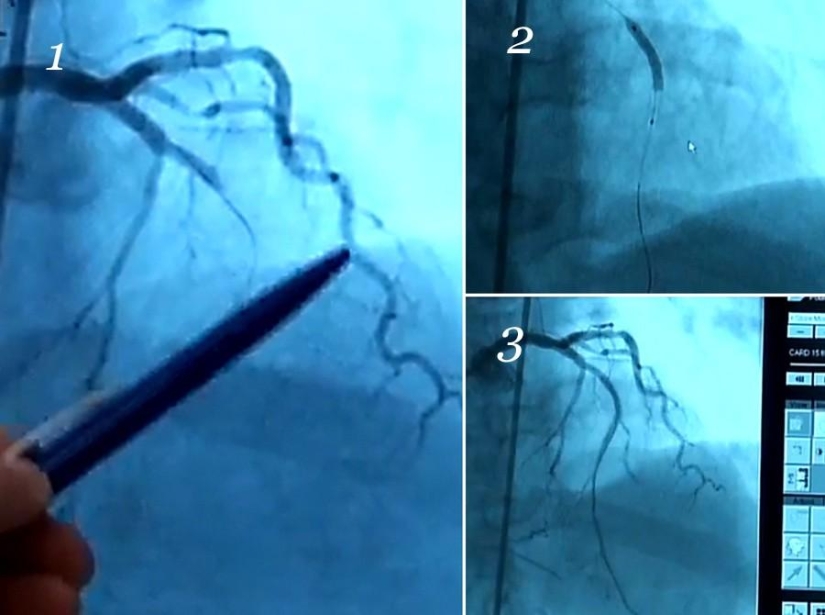

15. Y así es como funciona el stent. Estas son capturas de pantalla del televisor de rayos X.

En la primera imagen, vemos solo una arteria, una rizada. Pero otro debería ser visible, debajo de él. Debido a la placa, el flujo de sangre está completamente bloqueado.

La salchicha gruesa en el segundo es un stent que acaba de ser desplegado. Las arterias no son visibles porque el medio de contraste no corre por ellas, pero los cables son apenas visibles.

El tercero muestra el resultado. Apareció una arteria, manó sangre. Ahora compare la primera imagen con la tercera de nuevo.